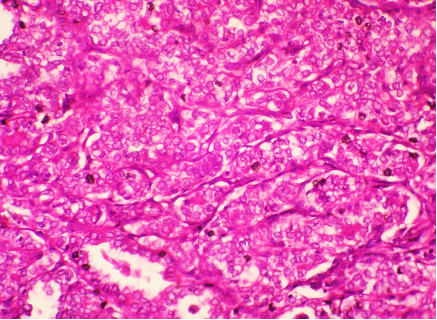

Ultrasonically guided fine needle aspiration cytology of a mass in front of the neck of a 40 year old female. Patient complained of severe back ache and had osteoporosis. Fig 1 and Fig 2 : are shown. Make your diagnosis.

Fig 1

Fig 2

Ans to previous (March 2025):

Excision of the specimen showed a cystic neoplasm (Figs A and B)

Diagnosis: Parathyroid adenoma .